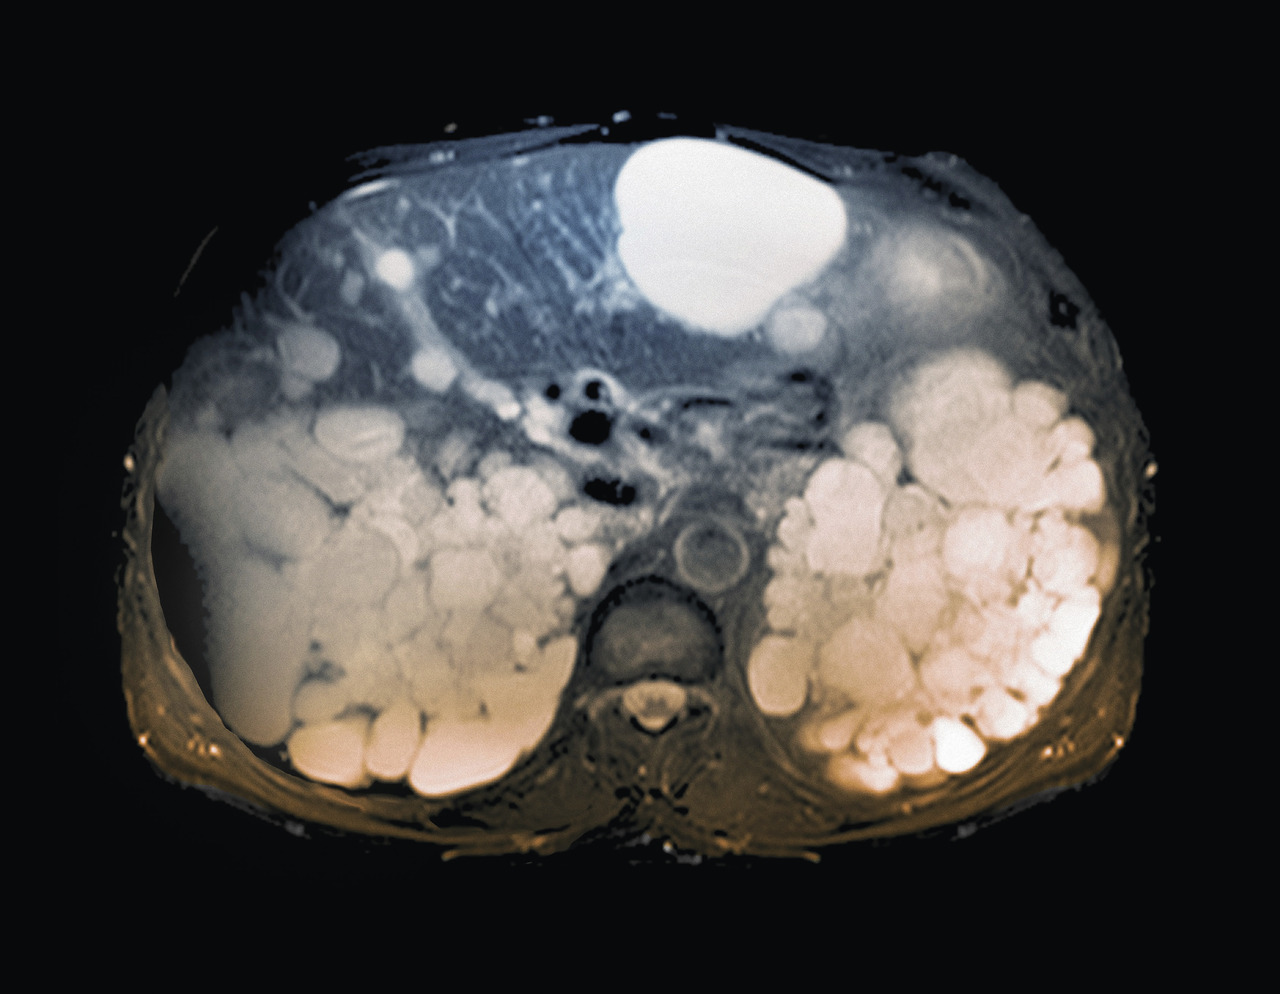

La polykystose rénale autosomique dominante (PKRAD) est la maladie rénale héréditaire la plus fréquente : sa prévalence est estimée autour de 1 pour 2 000 personnes dans le monde. Dans 90 % des cas, elle est liée à des mutations des gènes PKD1 (les plus fréquentes) ou PKD2 (formes moins sévères). Elle se caractérise par le développement progressif de kystes rénaux et une augmentation du volume rénal total (VRT), ce qui entraîne des anomalies de la concentration des urines, une HTA, une polyurie, une nocturie, des douleurs, des lithiases rénales, des épisodes d’hématurie, des infections kystiques et un déclin progressif de la fonction rénale. Elle évolue habituellement vers l’insuffisance rénale chronique terminale (IRCT) : 70 % des patients PKRAD sont dialysés (hémodialyse ou dialyse péritonéale) ou greffés à l’âge de 70 ans.1Jusqu’à récemment, il n’existait pas de traitement spécifique, en dehors de la prise en charge de l’HTA et des consignes hygiénodiététiques : boissons abondantes et bien réparties sur 24 heures, limitation des apports alimentaires sodés (NaCl < 6 g/j) et protéiques (0,8 g/kg/j). Depuis quelques années, de nouvelles molécules sont à l’étude, avec l’objectif de ralentir le développement des kystes et l’évolution de l’insuffisance rénale.

Des kystes hépatiques se développent chez plus de 80 % des patients, de façon plus marquée chez les femmes que chez les hommes, surtout après 45 ans (effet probable des hormones féminines).5 Les symptômes les plus fréquents sont liés à la compression des organes de voisinage avec, à l’extrême, des tableaux de cholestase, d’hypertension portale, de compression cave, de dyspnée chronique sur syndrome restrictif liée au volume hépatique. Les kystes se compliquent parfois d’infection ou d’hémorragie. La prise en charge, spécialisée, est décidée au cas par cas.

La PKRAD est évoquée le plus souvent chez un adulte jeune, devant une symptomatologie rénale (douleur, hématurie, lithiase, HTA, IR) ou lors de la découverte de kystes rénaux bilatéraux à l’échographie, soit lors d’une enquête familiale, soit de façon fortuite. Pour faire le diagnostic, l’echographie rénale est l’examen de 1re intention. Elle peut être faussement négative jusqu’à 30-40 ans. L’IRM rénale et le dépistage génétique sont parfois proposés. Un patient PKRAD a 50% de risque de transmettre la maladie à son enfant (quel que soit son sexe).